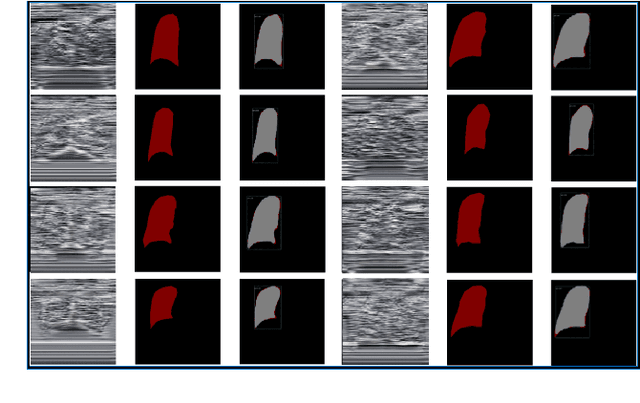

Abstract:The identification of nerve is difficult as structures of nerves are challenging to image and to detect in ultrasound images. Nevertheless, the nerve identification in ultrasound images is a crucial step to improve performance of regional anesthesia. In this paper, a network called Brachial Plexus Multi-instance Segmentation Network (BPMSegNet) is proposed to identify different tissues (nerves, arteries, veins, muscles) in ultrasound images. The BPMSegNet has three novel modules. The first is the spatial local contrast feature, which computes contrast features at different scales. The second one is the self-attention gate, which reweighs the channels in feature maps by their importance. The third is the addition of a skip concatenation with transposed convolution within a feature pyramid network. The proposed BPMSegNet is evaluated by conducting experiments on our constructed Ultrasound Brachial Plexus Dataset (UBPD). Quantitative experimental results show the proposed network can segment multiple tissues from the ultrasound images with a good performance.

Abstract:Internet of Medical Things (IoMT) can connect many medical imaging equipments to the medical information network to facilitate the process of diagnosing and treating for doctors. As medical image contains sensitive information, it is of importance yet very challenging to safeguard the privacy or security of the patient. In this work, a deep learning based encryption and decryption network (DeepEDN) is proposed to fulfill the process of encrypting and decrypting the medical image. Specifically, in DeepEDN, the Cycle-Generative Adversarial Network (Cycle-GAN) is employed as the main learning network to transfer the medical image from its original domain into the target domain. Target domain is regarded as a "Hidden Factors" to guide the learning model for realizing the encryption. The encrypted image is restored to the original (plaintext) image through a reconstruction network to achieve an image decryption. In order to facilitate the data mining directly from the privacy-protected environment, a region of interest(ROI)-mining-network is proposed to extract the interested object from the encrypted image. The proposed DeepEDN is evaluated on the chest X-ray dataset. Extensive experimental results and security analysis show that the proposed method can achieve a high level of security with a good performance in efficiency.